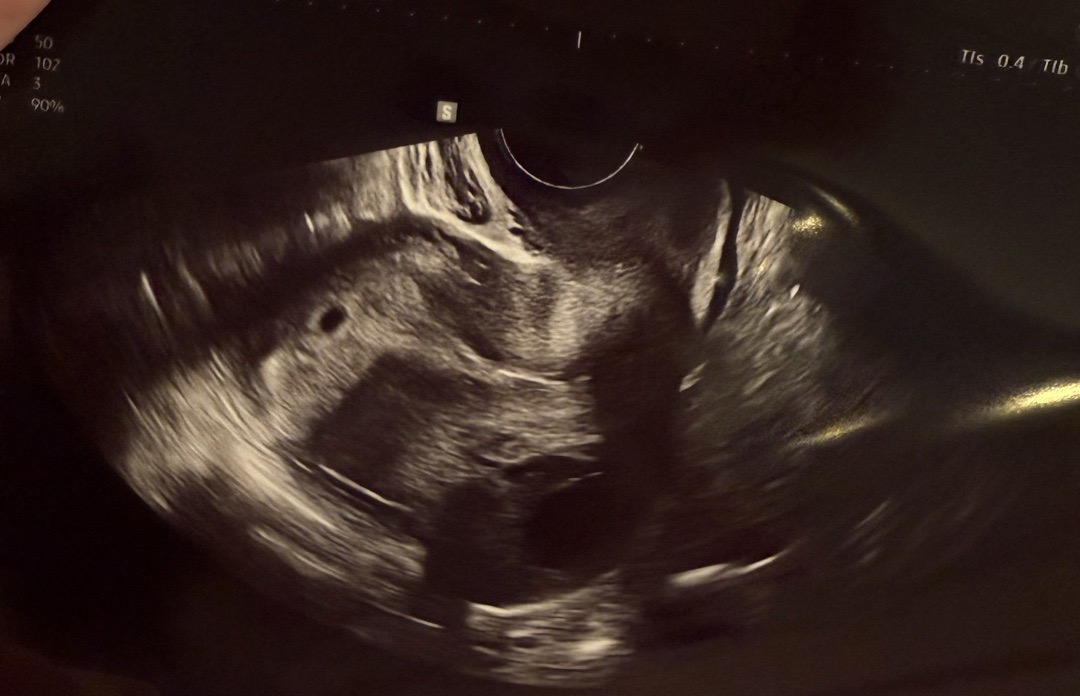

막생 5/28, 배란 6/14 아기집이 0.28cm인데 괜찮나요?

5주 5일차예요 인터넷 다른 분들 글 찾아보고 지인들도 이맘때는 아기집도 잘 보이고 난황?도 보이는데, 전 오늘 산부인과 갔는네 의사쌤이 집 아주 작게 보이네요 2mm 좀 넘는다고(0.28cm) 하시더라고요! 6/28에 피검수치 36, 6/30에 150이었구요! 괜찮은 거죠? ㅜㅜㅜ 걱정이 머릿속 가득해요ㅠ

저도 막생 5/28이고 지난주금요일날 0.26cm 아기집만 겨우봤어요! 배란이 늦게된건지 사이즈로는 5주0일이라고하셨어요!! 저도걱정해서 2주뒤오라는거 1주일뒤 가기로했어요~ 하루하루 시간이 왤케 더딘지..ㅎ 맛있는거 많이드시고 다음주에 한번더 걱정마시고 가보세요 ㅎㅎ 많이자라있을거에요 !!